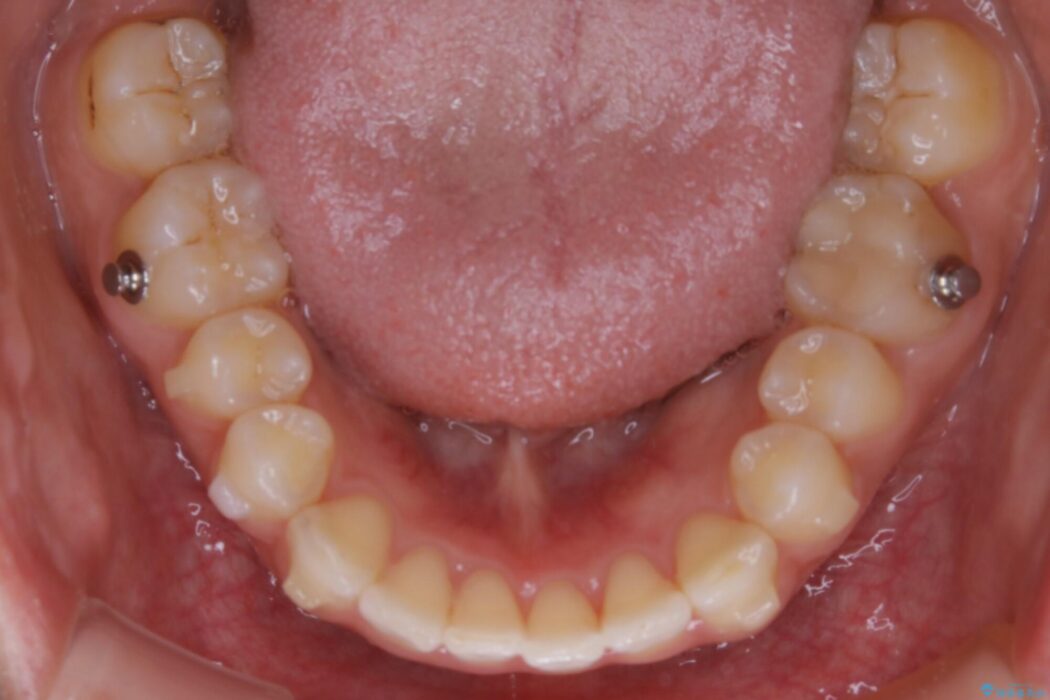

下顎前歯のガタつきを気にされて来院されました。

目立ちにくい矯正装置をご希望でしたのでマウスピースでの治療をご提案しました。

叢生の度合いにより抜歯は不要と判断しましたので、歯列幅の拡大を主軸に置き矯正治療を行いました。

本症例では下顎の歯列が舌側へ傾くことにより幅が狭まっていましたので、マウスピース治療により歯列弓を拡大しました。